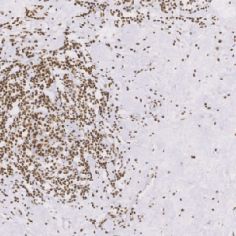

ERCC1免抗人ERCC1单克隆抗体

ERCC1是核昔酸切除修复通路中高度保守的切除性核酶,是有效修复烷化剂诱导的DNA复合物的必要条件。ERCC1蛋白阳性的患者非化疗治疗的预后要好于接受化疗。

- 阳性部位:胞核

- 适用组织:石蜡切片

- 预处理:热修复